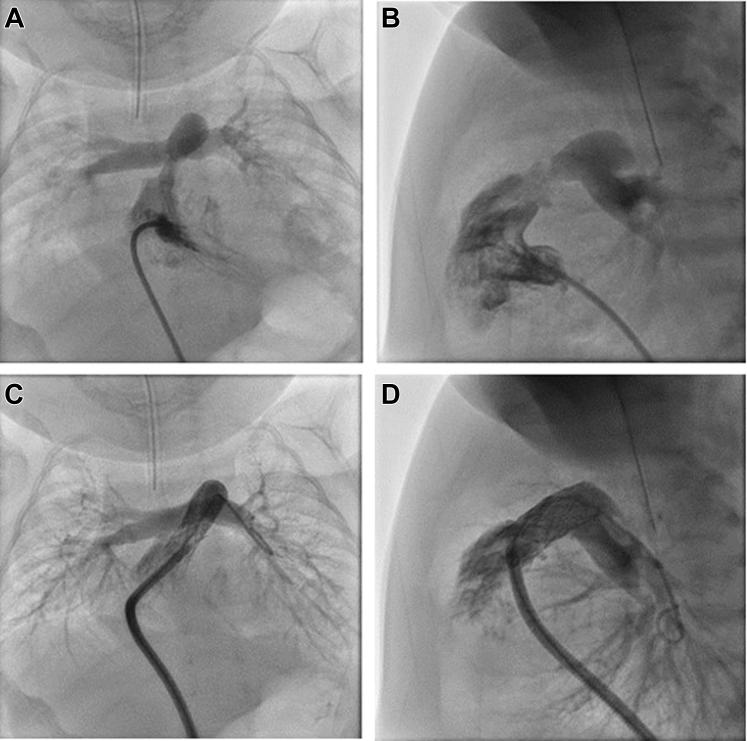

We describe an infant with a history of extreme prematurity, Noonan syndrome, hypertrophic cardiomyopathy, and severe valvular and supravalvular pulmonic stenosis who underwent right ventricular outflow tract stenting and mitogen-activated protein kinase kinase (MEK) inhibitor therapy.

我们描述了一名有极早早产史、努南综合征、肥厚型心肌病以及严重瓣膜和瓣膜上肺动脉狭窄病史的婴儿,该婴儿接受了右心室流出道支架置入术和丝裂原活化蛋白激酶激酶(MEK)抑制剂治疗。